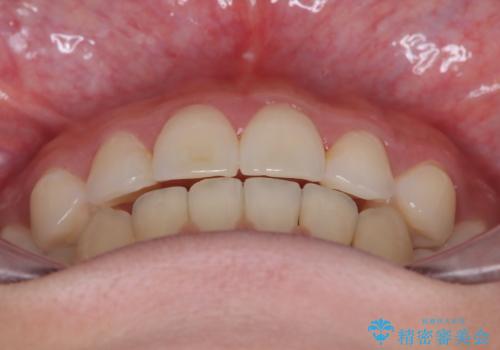

- 八重歯を主訴に来院された患者様です。

インビザラインによる矯正を希望され、今回は移動距離が少なくなるように犬歯を抜歯する治療計画としました。

抜歯矯正において、通常では4番(第一小臼歯)が抜歯の対象となることが多いのですが、今回は3番(犬歯)の歯肉退縮や装置の特性を考慮した治療計画となります。

下顎に関しては、半年ほどワイヤー矯正にてリカバリーを行なっております。